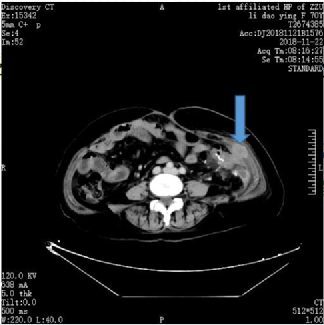

图2.2018年11月22日复查CT

当时我中心正在进行恩沃利单抗II期临床试验,该患者的基因检测结果显示为MSI-H,于2019年2月通过筛选后该患者入组“恩沃利单抗治疗dMMR/MSI-H 晚期结直肠癌及其他晚期实体瘤患者的临床疗效和安全性的多中心II期临床研究”。2019年3月起,为患者进行恩沃利单抗150mg,皮下注射,QW治疗,2019年5月7日复查CT显示,病灶显著缩小,疗效评估为部分缓解(PR)。该患者半年后复查CT提示腹壁及腹腔结节几乎完全消失,疗效评估为CRu。